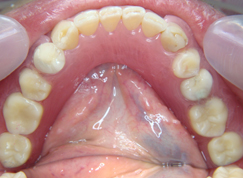

入れ歯は残っている歯に針金を引っ掛けるのが欠点。歯に負担をかけ見た目にも入れ歯と分かってしまう。針金を使わない入れ歯なら見た目だけではなく、歯にも負担が少ないですよ。

- 施術前

- 施術後